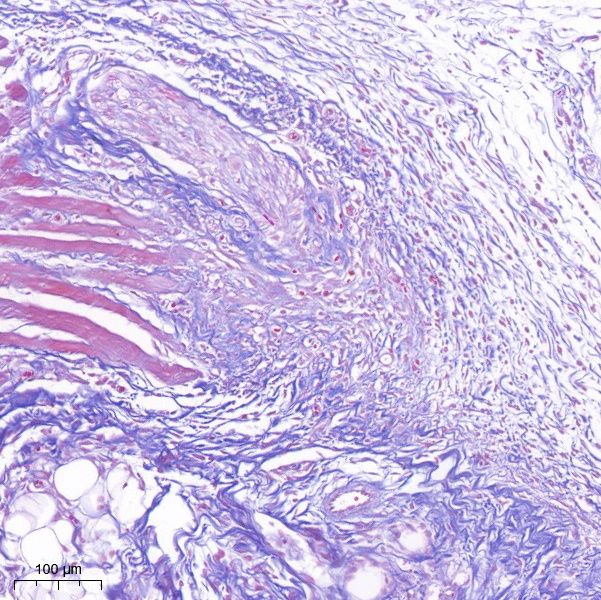

Masson染色

Masson染色,也称为马松染色,是一种广泛应用于观察组织纤维化的经典结缔组织染色方法。它通过特殊的染色步骤和染色剂,能够清晰地区分并显示组织中的胶原纤维和肌纤维,为研究人员提供了深入了解细胞和组织结构、形态及变化的重要工具。

其中,胶原纤维通常呈现为蓝色,而肌纤维则呈现为红色。

※实验结果示例:

胶原纤维通常呈现为蓝色,而肌纤维则呈现为红色。

masson染色·皮